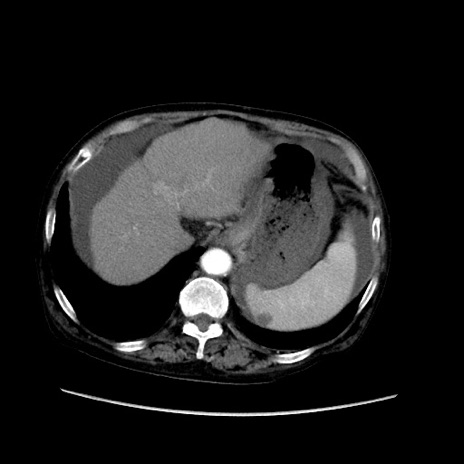

矢状断像

【症例】80歳代 女性

【主訴】腹部膨満感

【現病歴】他院にて肝硬変にてフォロー中。1週間前から便秘、腹部膨満感、臍部腫瘤あり受診となる。

【既往歴】肝硬変

【身体所見】腹部膨隆あり、皮膚変化なし、疼痛なし。

【データ】WBC 4600、CRP 0.25